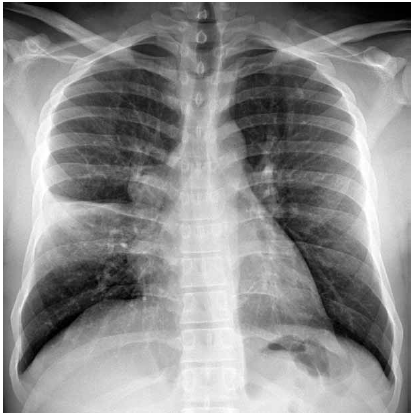

Homem de 24 anos de idade, sem antecedentes patológicos, apresenta-se à unidade básica de saúde com quadro de febre, dispneia e tosse com expectoração amarelada há 3 dias. Ele nega náuseas, vômitos, dor abdominal, diarreia, uso de medicamentos, tabagismo, etilismo ou uso de drogas. Exame físico: consciente, corado, hidratado e anictérico; PA: 115 x 75 mmHg, FC: 98 bpm, T: 38,6 ºC, FR: 16 ipm e SatO2: 96%; abdome: indolor; exame cutâneo e extremidades sem alterações relevantes. A radiografia realizada é mostrada a seguir.